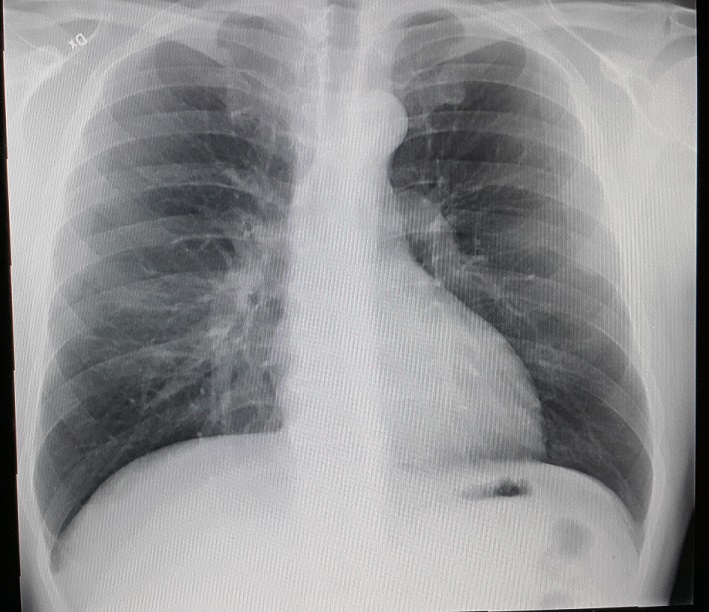

rontgen

Abrechnung – Teil 3